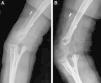

Caso 2Paciente de sexo masculino, de 26 años, diestro e ingeniero mecánico. Antecedente de accidente de tránsito como conductor de motocicleta, donde sufrió luxofractura transolecraneana de codo izquierdo y fractura diafisiaria de radio proximal. Se realizó osteosíntesis en otra ciudad con placa y pines, y se dejó inmovilizado durante 6 meses (fig. 3). Posteriormente consultó en nuestra institución con el codo rígido y relató dolor intenso. Se le intervino en un primer tiempo quirúrgico. Se le retiró el material de osteosíntesis y se tomaron muestras para cultivo, que quedaron con defecto de cobertura posterior. En los cultivos de hueso se aisló Staphylococcus aureus sensible a oxacilina y el paciente recibió tratamiento antibiótico completo. En conjunto con cirugía plástica se decidió esperar la cicatrización por segunda intención del defecto en piel y posponer la nueva fijación hasta obtener cobertura completa.

El paciente actualmente completa 18 meses de seguimiento clínico y radiológico con evidencia de consolidación completa, sin recaída infecciosa y reintegro completo a sus actividades laborales. Se encuentra satisfecho con el procedimiento desde el punto de vista funcional y estético (fig. 5).